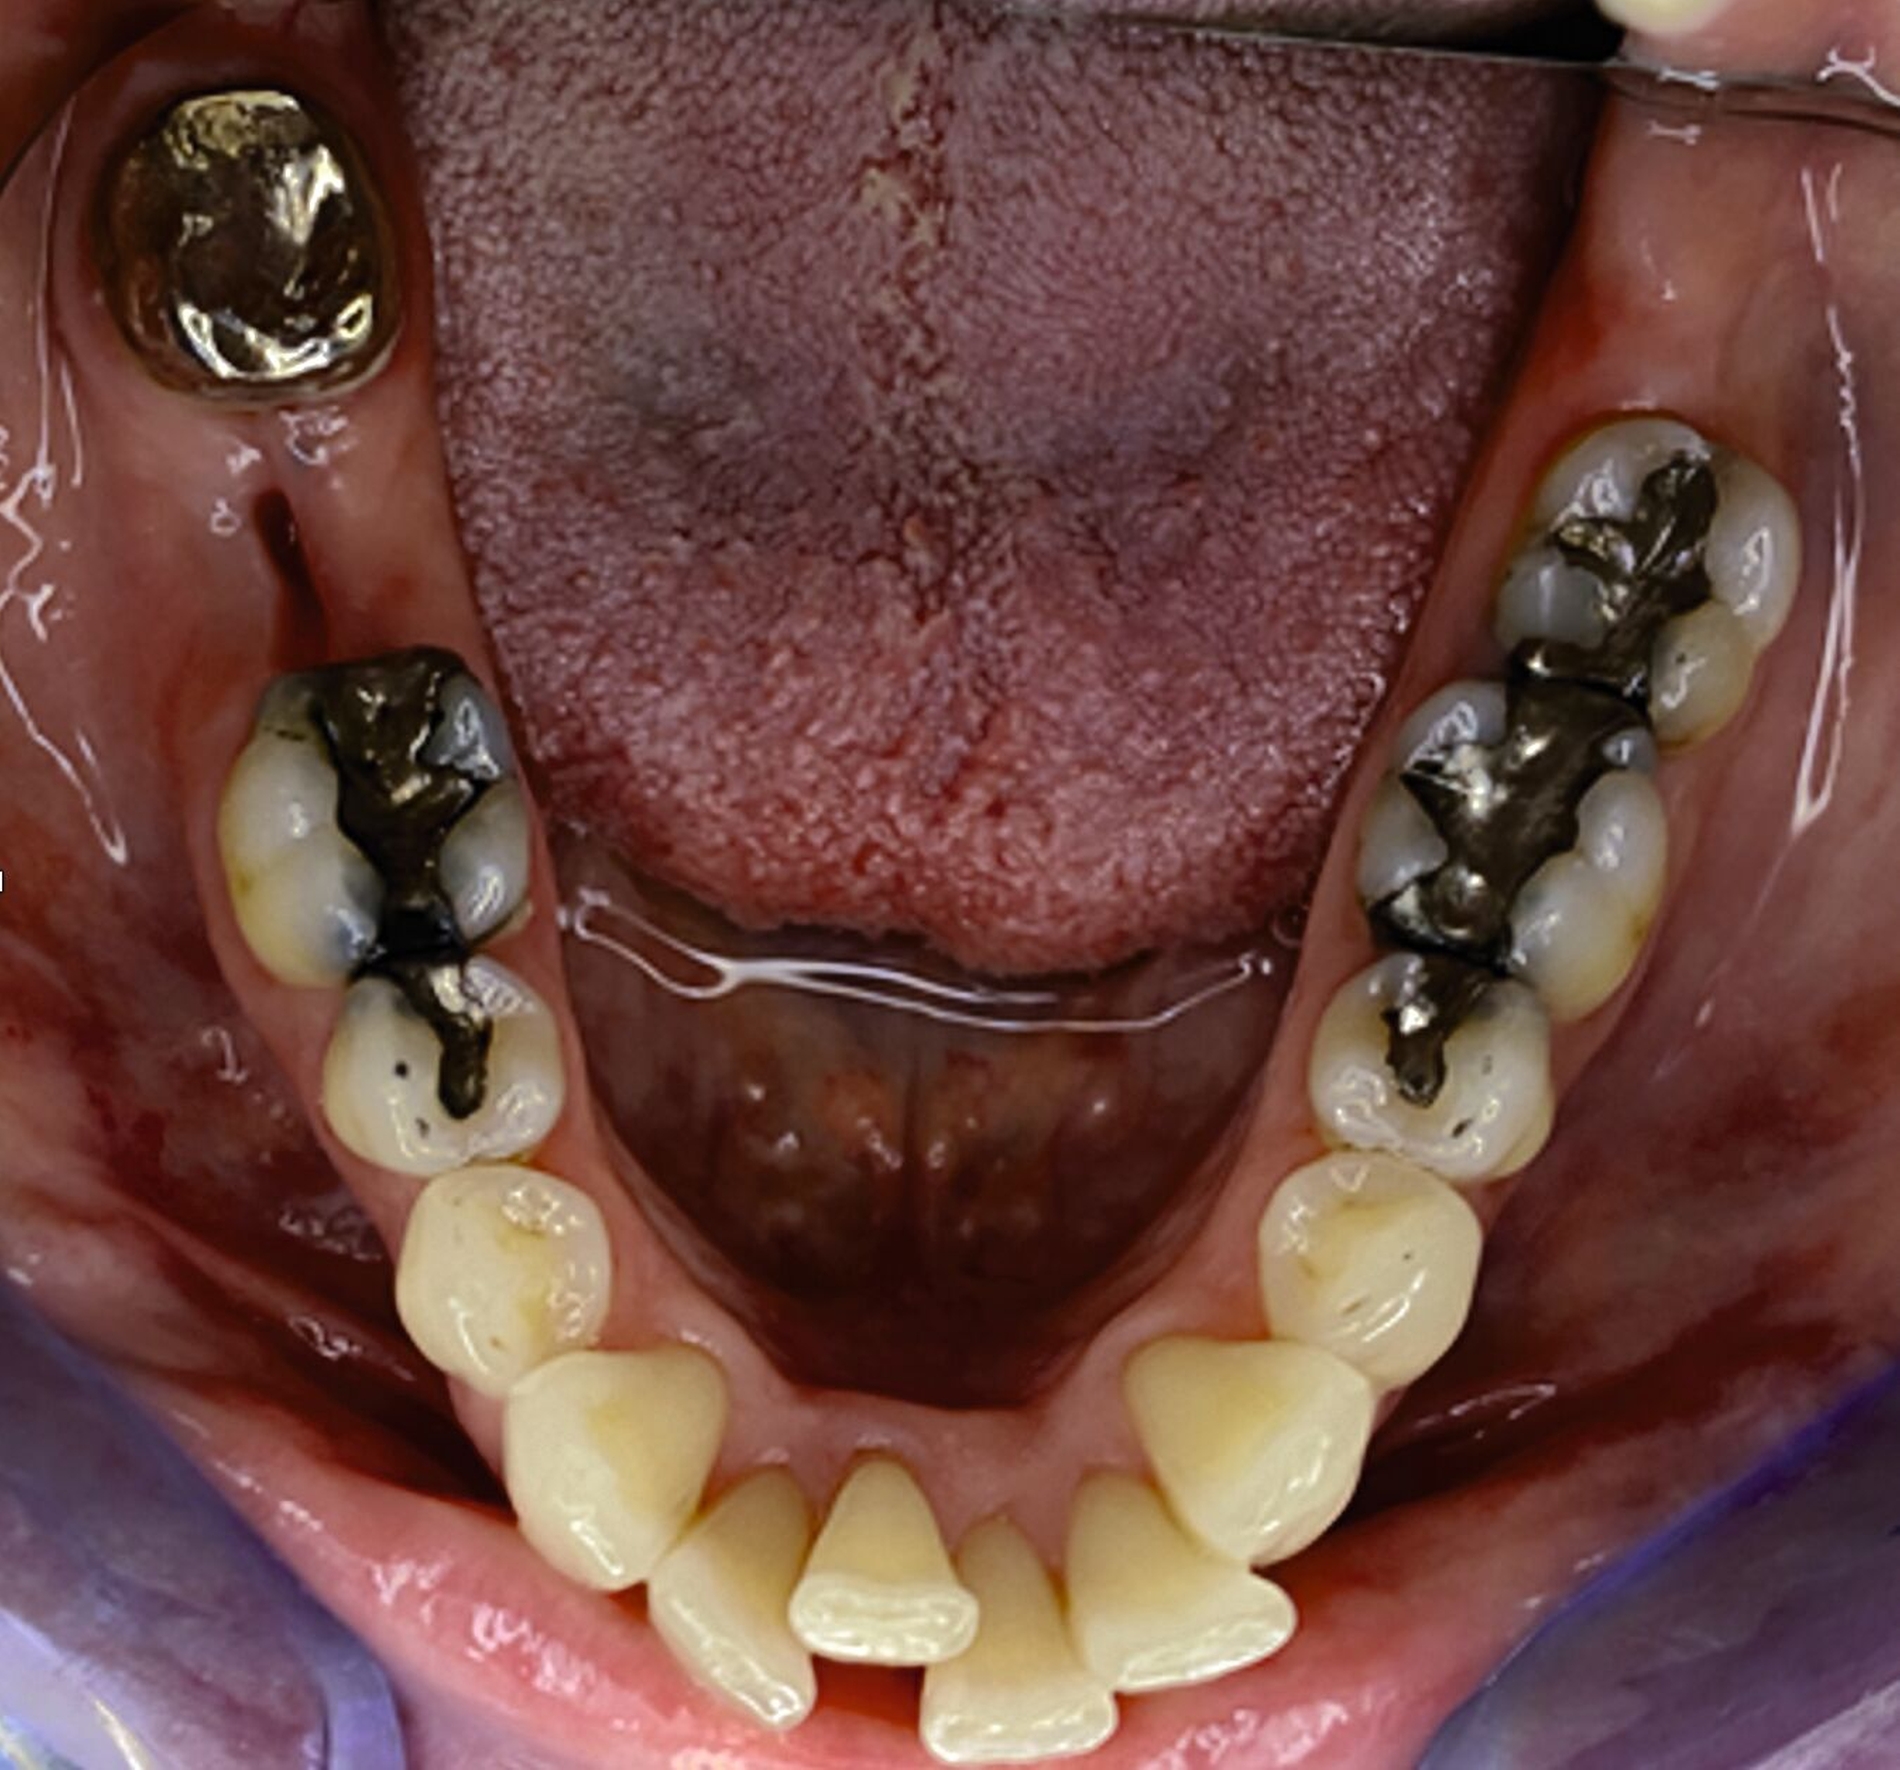

Klinisch zeigten sich diverse großflächig, mehrheitlich mit Amalgam gefüllte Seitenzähne, suffiziente endodontische Behandlungen an den Zähnen 16 und 14 sowie intakte Kronen an den Zähnen 16 und 48 (Abbildung 2). Ein Parodontaler Screening-Index (PSI) wurde erhoben (1-1-0-0-2-1), der stabile Verhältnisse nachwies. Das funktionelle CMD-Screening zeigte eine nicht-druckdolente Kaumuskulatur sowie eine uneingeschränkte Mundöffnung ohne Reiben und Knacken.

Tabelle 1 zeigt das entsprechende Befundschema mit den Taschentiefen mesial und distal, den Lockerungsgraden und den Sensibilitätsüberprüfungen mittels Kältespray (ViPr). Die Ruheschwebelage wurde mithilfe des Zielinsky-Zirkels auf 2 mm bestimmt. Die Nonokklusion im Seitenzahnbereich konnte auf circa 1,5 mm bemessen werden. Tabelle 2 spiegelt das entsprechende Okklusionsprotokoll wider. Das Okklusionsprofil wird auch in den Abbildungen 3a bis 3c deutlich.